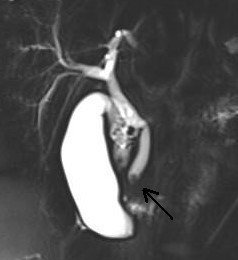

İzmir'in Torbalı ilçesinde yaşayan iki çocuklu Aslıhan Baytekin (36) ile Ersin Baytekin'in (37) büyük kızları Elif, yaklaşık iki yıl önce şiddetli karın ağrısı şikayetiyle hastaneye götürüldü. Safra kesesinde taş saptanan Elif, doktor takibine alındı. Ancak geçtiğimiz günlerde küçük kızda karın ağrısının yanında kaşıntı ve sarılık da başladı. Baytekin çifti, şikayetleri artan ve dayanılmaz hale gelen kızlarını İzmir Kent Hastanesine getirdi. Kent Hastanesinde Çocuk Cerrahı Doç. Dr. Tunç Özdemir, muayene ve tetkiklerden sonra Elif'e "safra yolu tıkanıklığı" tanısını koydu. 11 yaşındaki Elif, başarılı bir ameliyatla sağlığına kavuşurken, Doç. Dr. Özdemir ise "11 yaşındaki hastamızın bilirubin yüksekliği ve şiddetli ağrısı vardı. Yapılan tetkiklerde safra yolunun taş ile tıkanmış olduğunu saptadık. Hastanemiz Gastroenteroloji Uzmanı Prof. Dr. Ethem Tankurt ile birlikte kısaca ERCP (Endoskopik Retrograd Kolanjiyo Pankreatografi) denilen kapalı ameliyat yöntemi ve sfinkterotomi uyguladığımız hastamızın bilirubini düştü ve ağrısı geçti, şifa işe taburcu oldu" dedi.

Safra taşının sadece yetişkinlerde değil, çocuklarda da görüldüğünü açıklayan Doç. Dr. Özdemir, "Üstelik son 20 yılda görülme sıklığı arttı. Beslenme alışkanlıkları, bazı kan hastalıkları, ilaçlar taş oluşumunda önemli etkendir, obezite de önemli bir unsurdur. Safra kesesi taşları uzun süre bulgu vermeden kalabilir. Bazen safra kesesi iltihabına veya safra yoluna düşüp safra yolu tıkanıklıklarına neden olabilir. Safra yoluna düşmüş olan taşlar, şiddetli ağrı, sarılık ve pankreas bezi iltihaplarına yol açıp, hayati tehlike oluşturabilirler. Safra kesesi taşı, kapalı yöntemle sorunsuz bir şekilde ameliyat edilebilirken, safra yolu tıkanıklıkları endoskopi ile safra yolu girişimleri gerektirir. Çocuk ne kadar küçükse, girişim de o kadar zordur" diye konuştu.